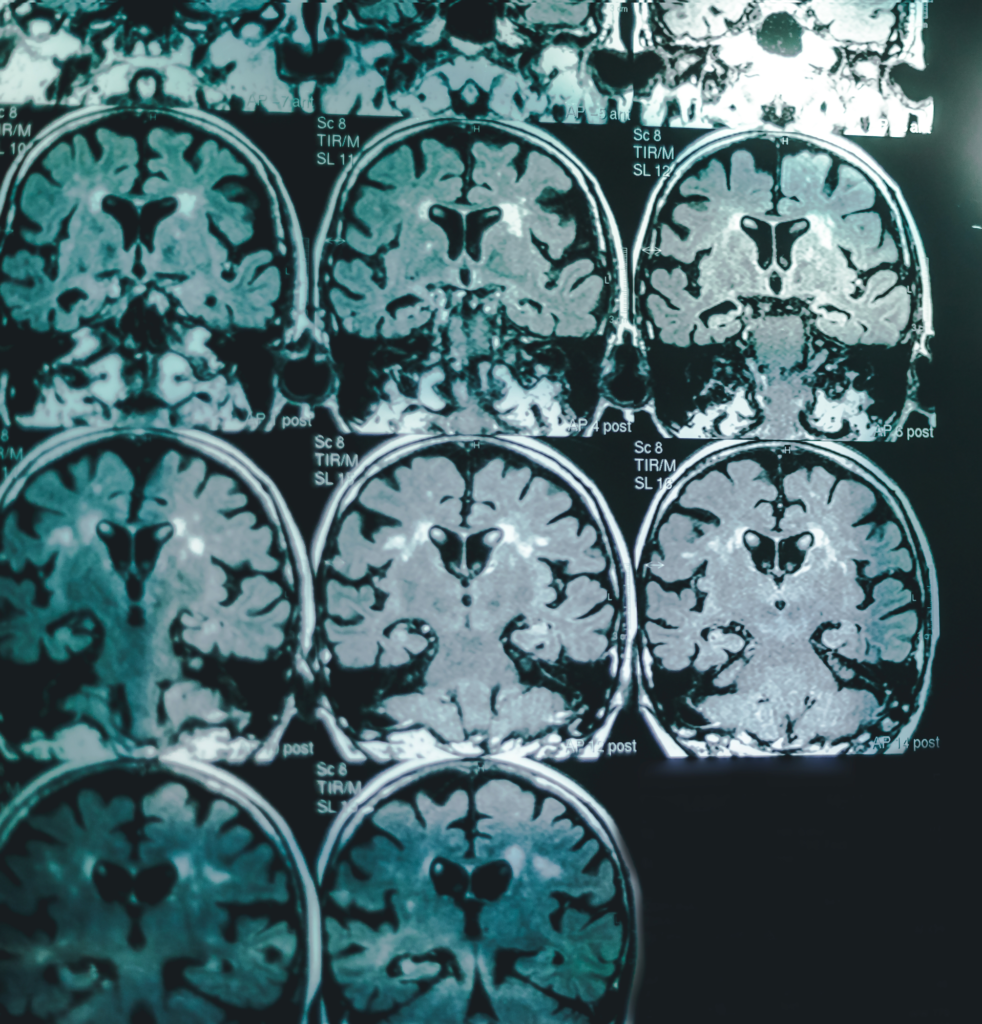

Brain Structure Preservation

Neuroimaging data from the AMBAR program show better preservation of hippocampal volume, reduced subcortical atrophy, and less metabolic decline on FDG-PET in treated patients, suggesting a protective structural effect on the brain.